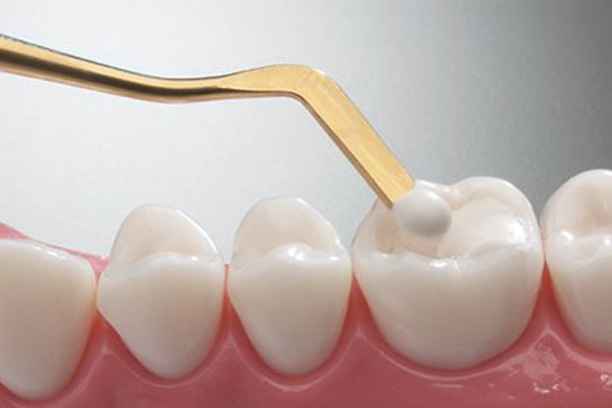

تمر عملية حشو الأسنان بخطوات دقيقة تضمن الراحة والدقة العلاجية، خصوصًا في مركز يعتمد معايير عالية مثل أضواء الحكمة. تشمل الخطوات:

- فحص سريري شامل لتحديد مدى التسوس وعمقه.

- تصوير شعاعي رقمي لتقييم الأنسجة الداخلية.

- تخدير موضعي مريح يضمن عدم الشعور بالألم.

- إزالة التسوس بعناية دون المساس بالأنسجة السليمة.

- تعقيم التجويف السني لمنع أي تلوث مستقبلي.

- وضع مادة الحشو بطبقات مدروسة.

- تشكيل الحشوة لتتوافق مع الإطباق الطبيعي.

- تثبيت الحشوة وصقلها للحصول على سطح أملس.

شرح خطوات حشو الاسنان خطوة بخطوة

تمر عملية حشو الأسنان بعدة خطوات أساسية لضمان دقة وراحة المريض:

- فحص شامل للأسنان واللثة بالأشعة الرقمية لتقييم التسوس وبنية الجذر.

- تنظيف التجويف وإزالة التسوس دون الإضرار بالأنسجة السليمة.

- تعقيم وتحضير السن لاستقبال مادة الحشو لضمان نجاح العملية.

- اختيار نوع الحشو المناسب حسب تشخيص الطبيب، مثل الحشوات الراتنجية أو السيراميكية.

- تطبيق الحشو بدقة على شكل طبقات متدرجة لاستعادة شكل ووظيفة السن.

- تشكيل وصقل الحشوة للحصول على سطح أملس ومتناسق مع الإطباق الطبيعي.

- التحقق من الإطباق والمضغ لتجنب الضغط غير المتوازن على الأسنان المجاورة.

- تقديم تعليمات متابعة للحفاظ على الحشوة ومنع أي مضاعفات مستقبلية.